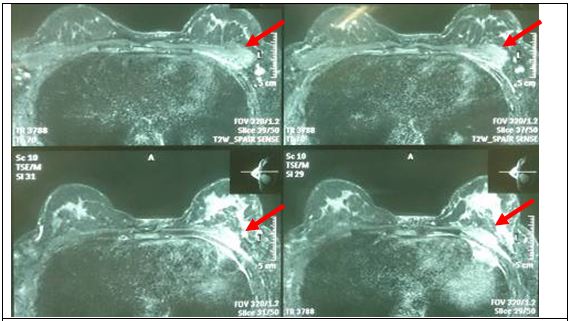

Chụp cộng hưởng từ tuyến vú hai bên: Tổn thương phần mềm thành ngực trái, thâm nhiễm xương sườn và nhu mô vú ½ trái, kích thước 52 x 19 mm, có vài hạch nhỏ tại nách hai bên.

Hình 4: Hình ảnh cộng hưởng từ tuyến vú hai bên: Tổn thương phần mềm thành ngực trái, thâm nhiễm xương sườn và nhu mô vú ½ dưới sát tổn thương, kích thước 52 x 19 mm (mũi tên), có vài hạch nhỏ tại nách hai bên